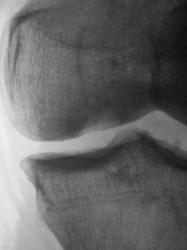

А вот примерно так выглядит это ложе на КТ, пока оно ещё не опустело (ложе в медиальном мыщелке помечено стрелками). Б-нь Кенига.